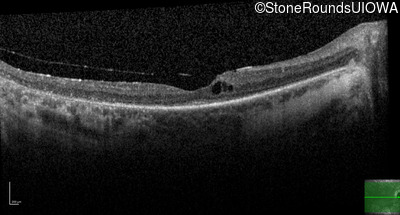

Age at visit: 53 years

This 53 year old woman first noticed night blindness at age 18. More recently she has experienced constriction of her visual fields. She has worn hearing aids since childhood.

Age at visit: 54 years